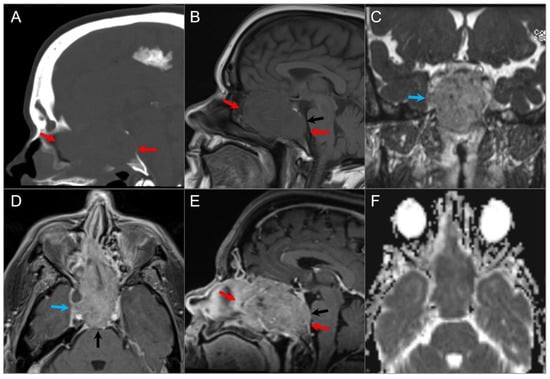

4.2.3. Olfactory Neuroblastoma

4.3. Central Skull Base Tumors

4.3.4. Cholesterol Granuloma